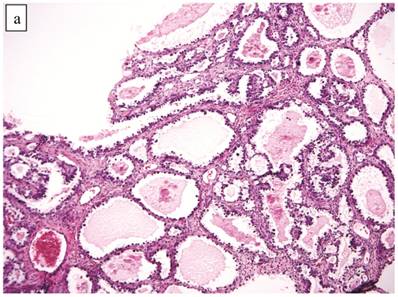

Figure 7

Atypical endometriotic cyst associated with clear cell carcinoma. (A) The endometriotic cyst contains scattered atypical epithelial cells, which were not directly contiguous with the carcinoma (not shown). (B) The atypical cells have round nuclei and abundant eosinophilic cytoplasm. Some atypical nuclei are hyperchromatic whereas others have irregularly distributed chromatin.

Associations with endometriosis, including comparison with adenofibromatous clear cell CAs, are shown in Tables 2, 3, and 5. The 57 CAs with endometriosis in the ovarian tumor had the following histologic patterns: tubulocystic (n=4), glandular (n=1), solid (n=4), and papillary (n=8). Mixed patterns occurred in 40. Thirty-one of the 46 (67%) cases arising directly within an endometriotic cyst had a predominantly cystic gross appearance. Foci of epithelial atypia in endometriosis in the ovarian tumor were similar to those in endometriosis associated with APTs noted above (Figs. 6 and 7).

The CA(AF-)s with endometriosis, which tended to be cystic, in the present study were significantly associated with atypical endometriosis. In some cases, there was a morphologic continuum within the epithelium of the endometriotic cyst, in which a gradual progressive transition between typical endometriosis, atypical endometriosis, and CA could be seen. It is noteworthy that prior studies have shown a higher frequency of atypia in endometriosis when a co-existent clear cell CA is present.17,42,50,70 Atypical endometriosis also exhibits a Ki-67 proliferation index intermediate between typical endometriosis and clear cell CA.72 A large number of molecular and chromosomal alterations have been identified in typical and atypical endometriosis/endometriotic cysts.2,3,21,26-28,32,36,48,57,67,69 Moreover, an atypical endometriotic cyst recurring as clear cell CA has been reported.46 These observations provide strong evidence that a subset of clear cell CAs arise via the development of atypia in an endometriotic cyst as opposed to non-cystic endometriosis.